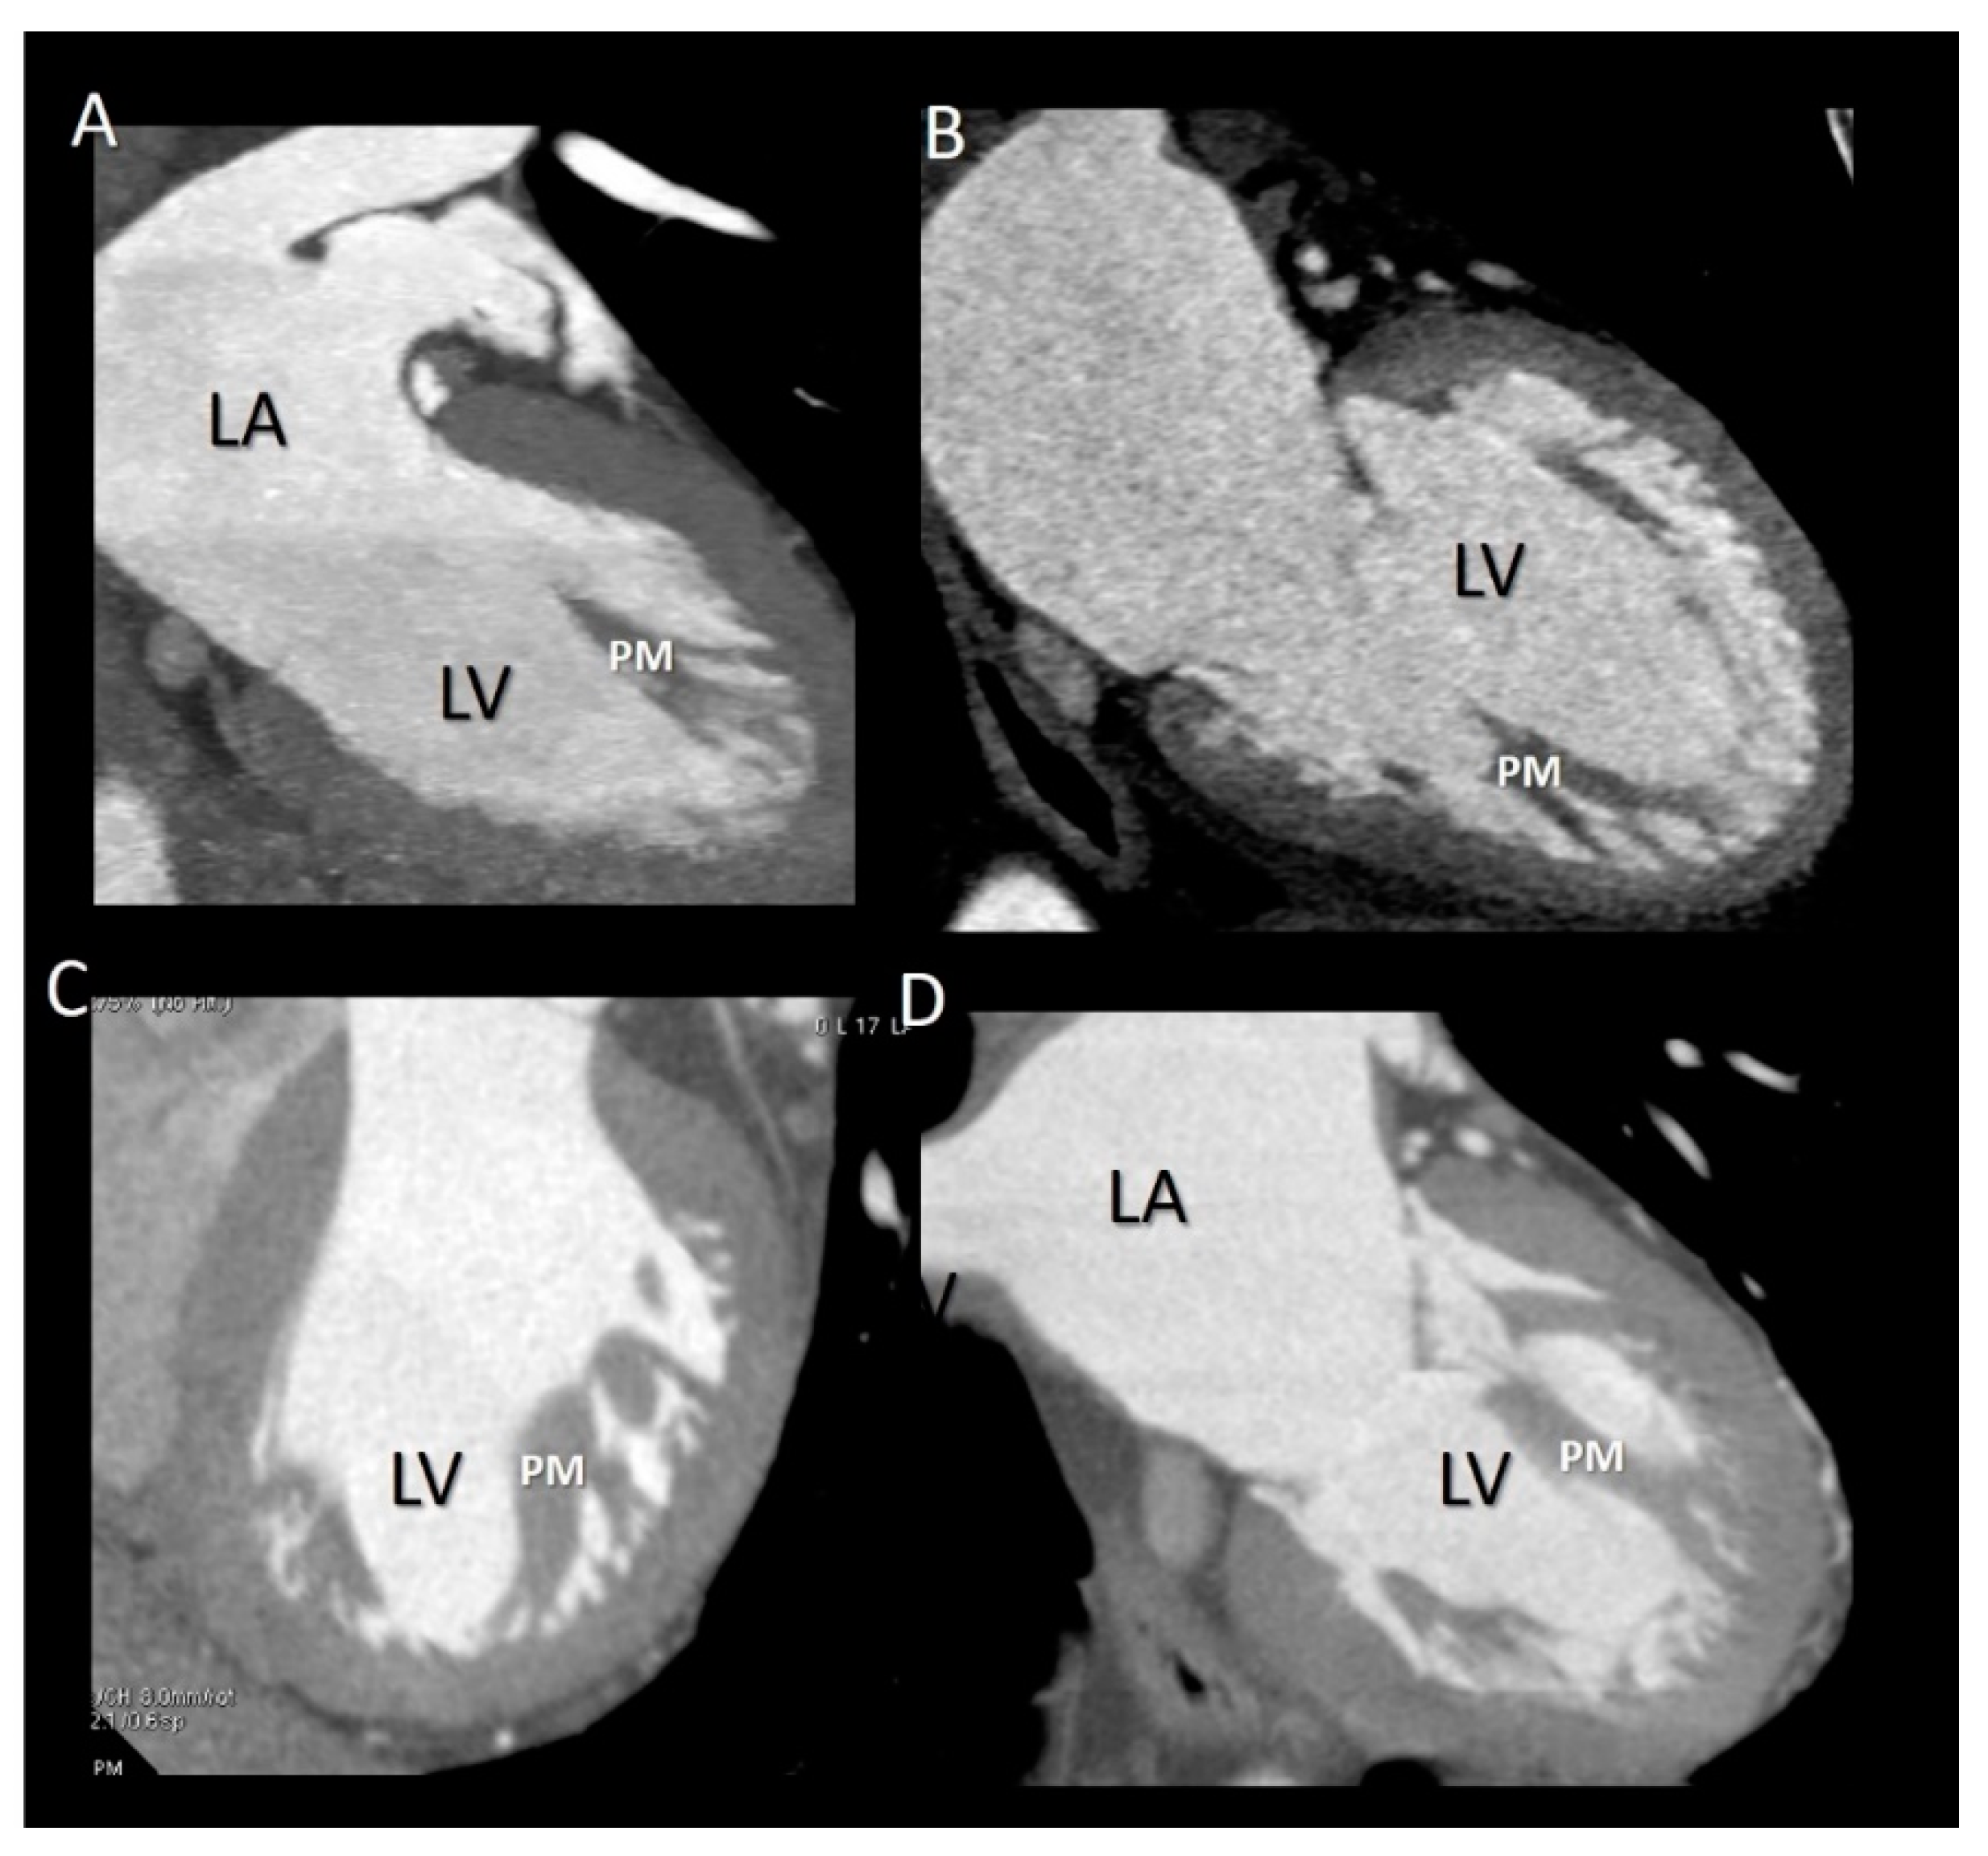

5. Papillary Muscles

Imaging Techniques